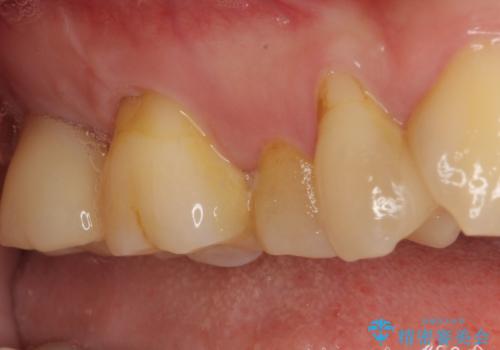

- 長年放置しているむし歯を気にして来院された患者様です。

外側を向いている上顎の奥歯は歯ブラシが十分に届かないため、むし歯となるケースが多いのですが、今回むし歯となってしまった歯がそれで、ボロボロになって根だけが残っている状態でした。

患者様と相談し、抜歯をした上でインプラントによる補綴治療を行うこととしました。